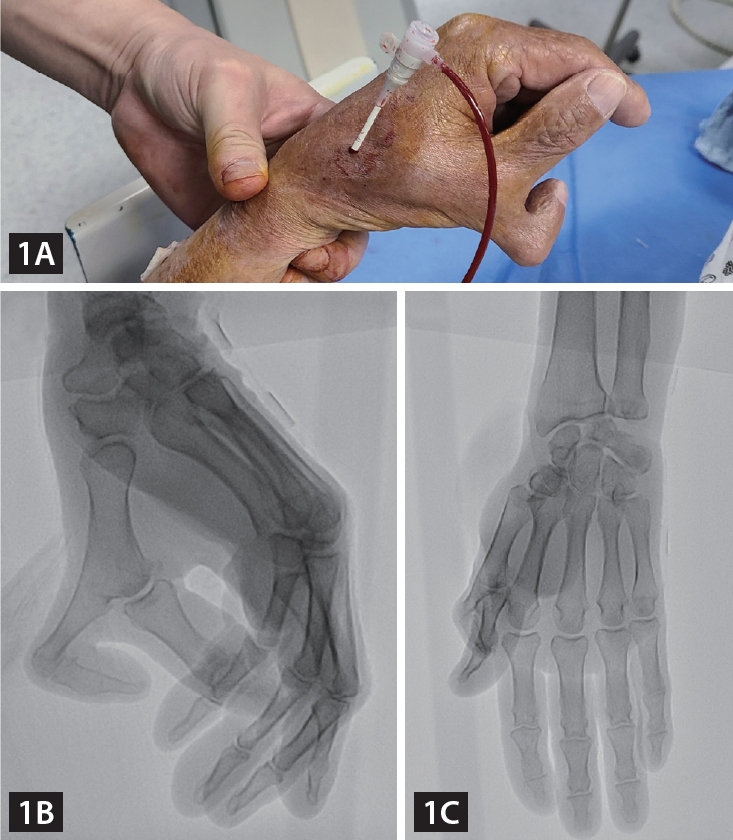

An 82-year-old male patient was admitted due to atypical chest pain, and he underwent coronary angiography (CAG) via a left distal radial access (DRA). We found that he had polydactyly of his left hand, which could be classified as Wassel Type 4 polydactyly (Fig. 1) [1]. We were concerned about the anatomical variation of the left distal radial artery due to the anomaly, but a distal radial pulsation was easily palpated in the anatomical snuff box, and a successful puncture was performed. A CAG was performed using a 5 Fr vascular access sheath 10 cm in length, according to the usual method, and it revealed mild narrowing (Supplementary Video 1-3). We wanted to determine the intact natural vascular anatomy of the polydactyly-affected hand; hence, we performed manual compression for 10 minutes after sheath removal and performed brachial angiography via brachial puncture with a 20G angiocath cannula. Angiography showed the usual run-off of the left distal radial artery through the anatomical snuff box, and there was an additional digital branch to the accessory thumb (Fig. 2, Supplementary Video 4). The puncture site was compressed for an additional two hours with a gauze block and simple elastic bandage to ensure complete hemostasis.